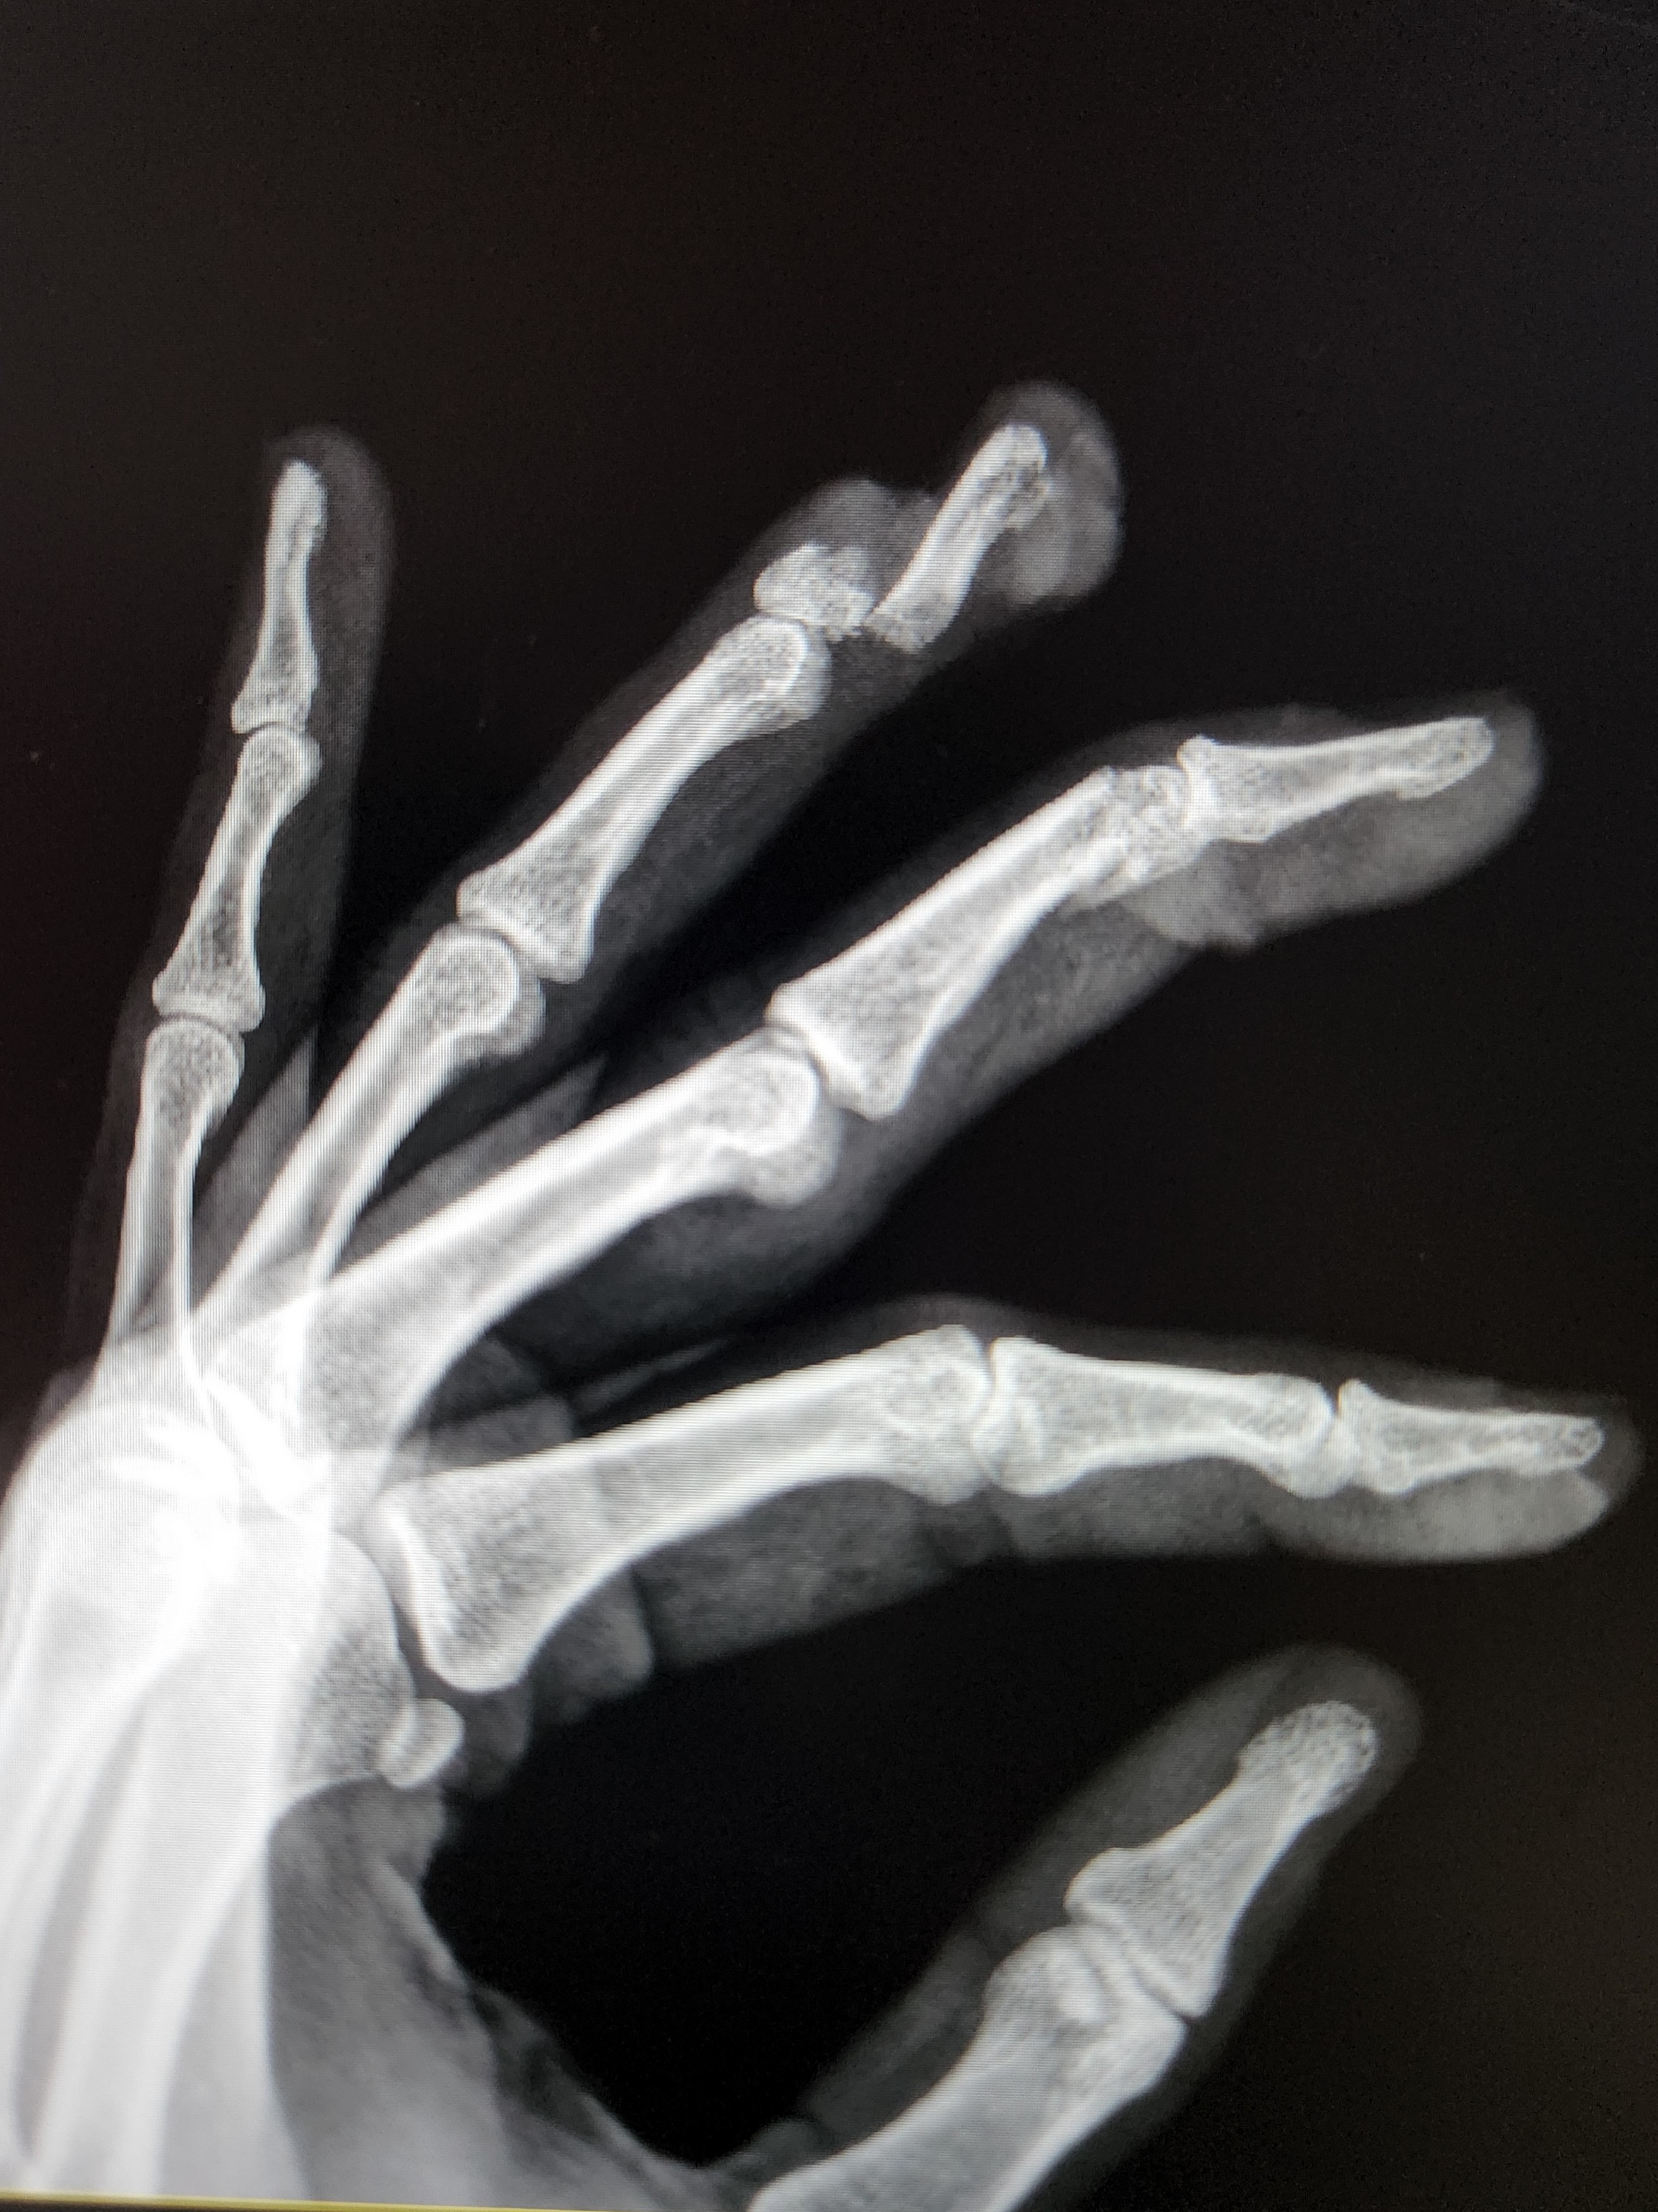

Emergency room x-rays revealed that the saw had entirely severed the bone of my ring finger, sliced halfway through the distal joint of my middle finger, and nicked the end of my index finger. Looking from the palm side of my hand, I could see the pale white bone of my ring finger. I was surprised by how small it is. Within two hours of injury, a nice ER resident doctor was stitching my fingertips back together. That was the most uncomfortable hour of my life thus far. It was a tricky process, as wrapping them in the towel had effectively stopped the blood loss, but they started bleeding again as we attempted to clean them up. Each needle prick for each stitch, brought more blood.

I watched him sew up the first two, but I couldn’t bear to look at my ring finger, as it was twisted sideways and hanging on only by some flesh on one side. I told him, “Please, doctor… do whatever you need to do, just make my finger look like a finger again.” He told me, “Well, that means I’ll have to pull it.” I said, “Okay, pull it,” and gritted my teeth. I didn’t feel him pull it, but he must have, because when he finally told me he was done, my fingertip was back in its proper place and alignment. I thanked him for saving my finger. He told me, lawyerlike, that it was probably too soon to say that he had saved anything. But I truly felt in my heart, that he had saved my ring fingertip that day.

When the attending ER doctor came by, he told me that I should expect the distal portion of my ring finger to die. He gave me the name and number of an orthopedic hand specialist and told me to call, in the morning, for a consult appointment. The specialist would determine whether and when to amputate. I was discharged around 10:30 PM, and I took my hydrocodone (pain) and Keflex (prophylactic antibiotic) prescriptions and went home.

When I saw him Friday morning after my injury, the hand surgeon was very surprised. He surprised me, too, when he told me that he had planned to amputate the distal joint of my middle finger as well as the distal joint of my ring finger. The ER doctors hadn’t made me aware of the severity of my middle finger’s injury— the place where the saw cut through was spongy bone at the end of the middle joint— a place where the bone was unlikely to re-grow. I hadn’t realized that I had two fingers on the chopping block! He asked whether I could move my fingertips, and I was able to produce the tiniest wiggle, even from the distal joint of my middle finger. He told me that meant the tendons hadn’t been cut— somehow. Given that, added to the great color of my fingertips & nail beds and the fact that I had some sensation still, he told me that he saw no reason to amputate at that time. (And four months later, no amputation).